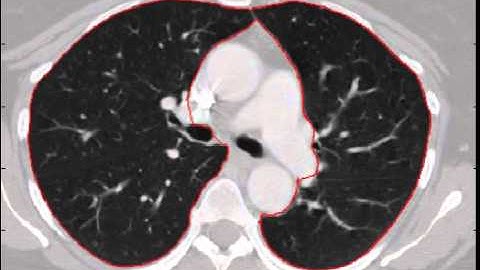

Matlab code for A Tool for Lung Nodules Analysis based on segmentation & morphological operations